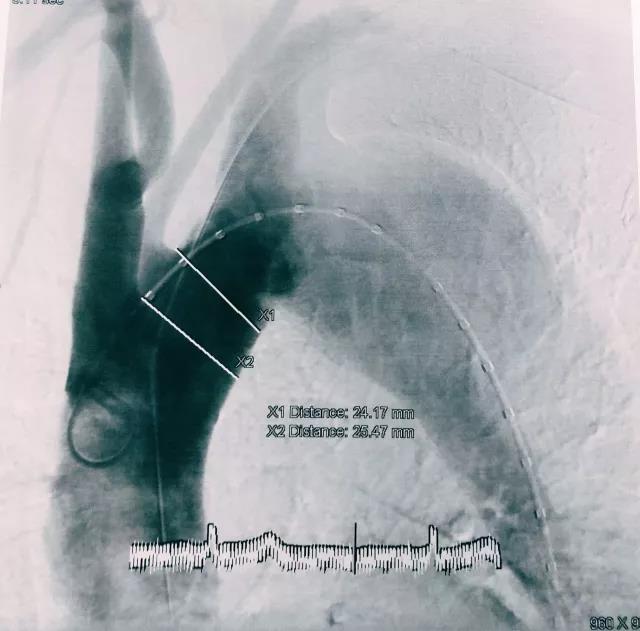

第二台手术为病变累及到左锁骨下动脉开口处的主动脉夹层患者。舒畅教授经过造影确认,决定将支架锚定于左锁骨下动脉和左颈总动脉之间,同时采用单烟囱技术保留左锁骨下动脉。舒畅教授将Ankura™ Pro主动脉主体覆膜支架定位在左颈总动脉的开口处释放后,再释放裙边支架,释放过程定位精确,左锁骨下血流畅通。舒畅教授通过对病例的观察,在原有的裙边支架远端植入了一个延长支架,最终造影显示动脉瘤完全隔绝,无内漏,术后结果完美。舒畅教授和印尼教授对先健主动脉覆膜支架系统表示了极大的赞赏。

(图:术后造影)